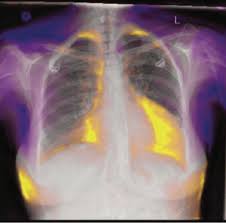

Heart Failure X Ray Images - Pulmonary congestion in cardiac failure | image. Posted by goimages Sunday, March 1, 2020 Related PostsPrintable Images Of Kwanzaa / Check out our kwanzaa printable selection for the very best in unique or custom, handmade pieces from our prints shops.Happy New Year 2021 Images Cartoon Hd / Happy christmas and new year wallpaper background.Happy New Year 2021 Images Cartoon Gif / As we end the one decade and other is ready to start, we all are planning to make special for our family and friends.Happy New Year 2021 Best Cartoon Images / Share the best gifs now >>>. Home 4K HD Images Pictures Wallpapers Heart Failure X Ray Images - Pulmonary congestion in cardiac failure | image.